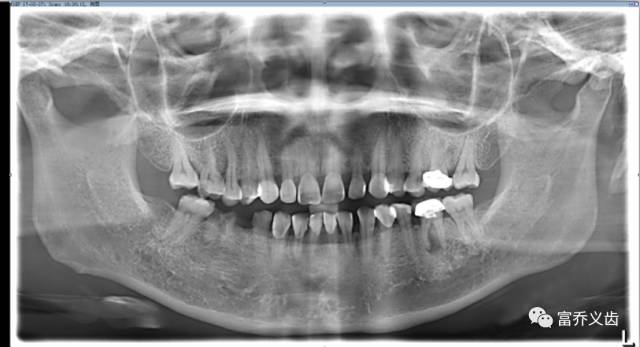

种植前曲面断层以及CBCT片